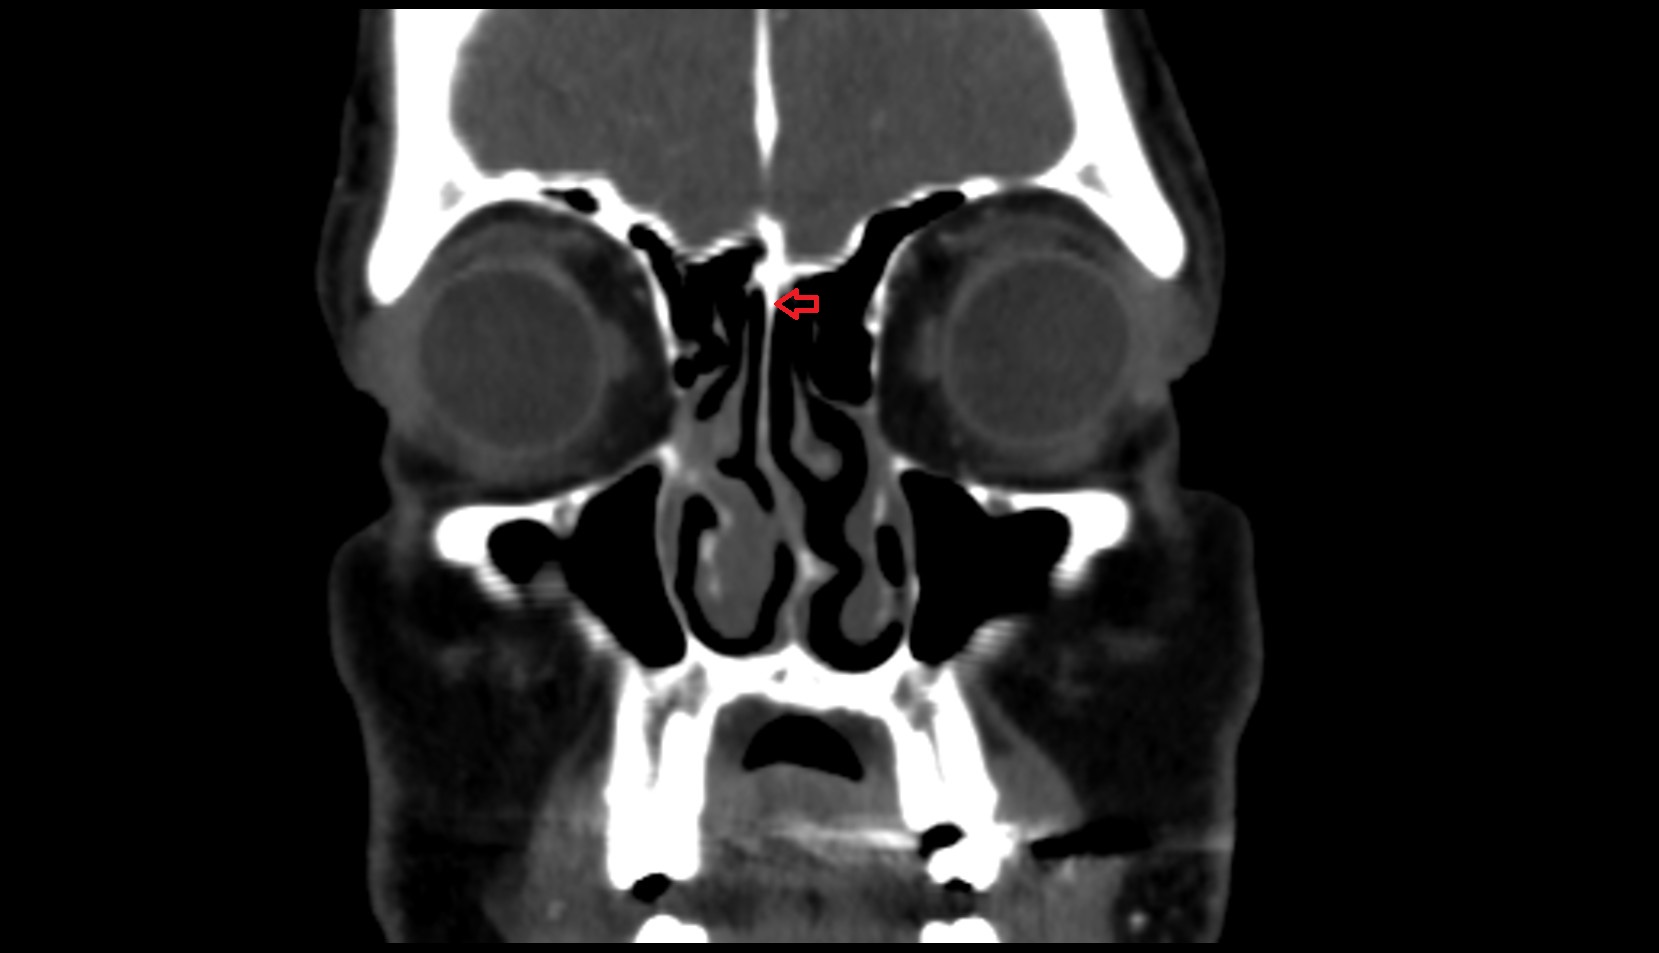

- Nasolacrimal duct (Tear duct)